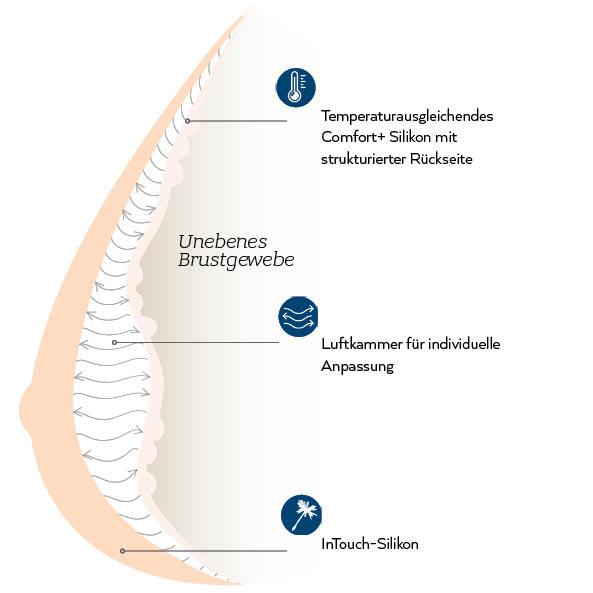

Ausgleichsformen sind Silikonformen, die Sie in Ihrem BH tragen, um so die Brustsymmetrie wiederherzustellen. Aufgrund vieler verschiedener Formen und Größen empfehlen wir Ihnen für die optimale Anpassung den Sanitätsfachhandel aufzusuchen. Unsere Ausgleichsformen werden aus hochwertigem Silikon hergestellt, dass für eine außergwöhnlich natürliche Passform und Gefühl auf der Haut sorgt. Zusätzlich nimmt unsere Comfort+ Technologie die Körperwärme auf, speichert sie und gibt sie wieder ab, um Schwankungen der Körpertemperatur zu regulieren und auszugleichen - für einen ultimativen Komfort den ganzen Tag lang.

Die Balance Adapt Air ist unsere bislang innovativste Ausgleichsform. Ihre integrierte Luftkammertechnologie ermöglicht es, die Ausgleichsform an Ihre individuellen Bedürfnisse

anzupassen. Mit Hilfe der Pumpe verändern Sie das Volumen der Ausgleichsform solange, bis diese der natürlichen Form Ihrer Brust entspricht und sie angenehm auf der Haut sitzt. Die Balance Adapt Air ist besonders dann für Sie geeignet, wenn Sie unter unebenem Narbengewebe, Ungleichheit der Brust nach einer OP, Gewichtsschwankungen oder an Schwellungen aufgrund eines Lyphödems leiden.